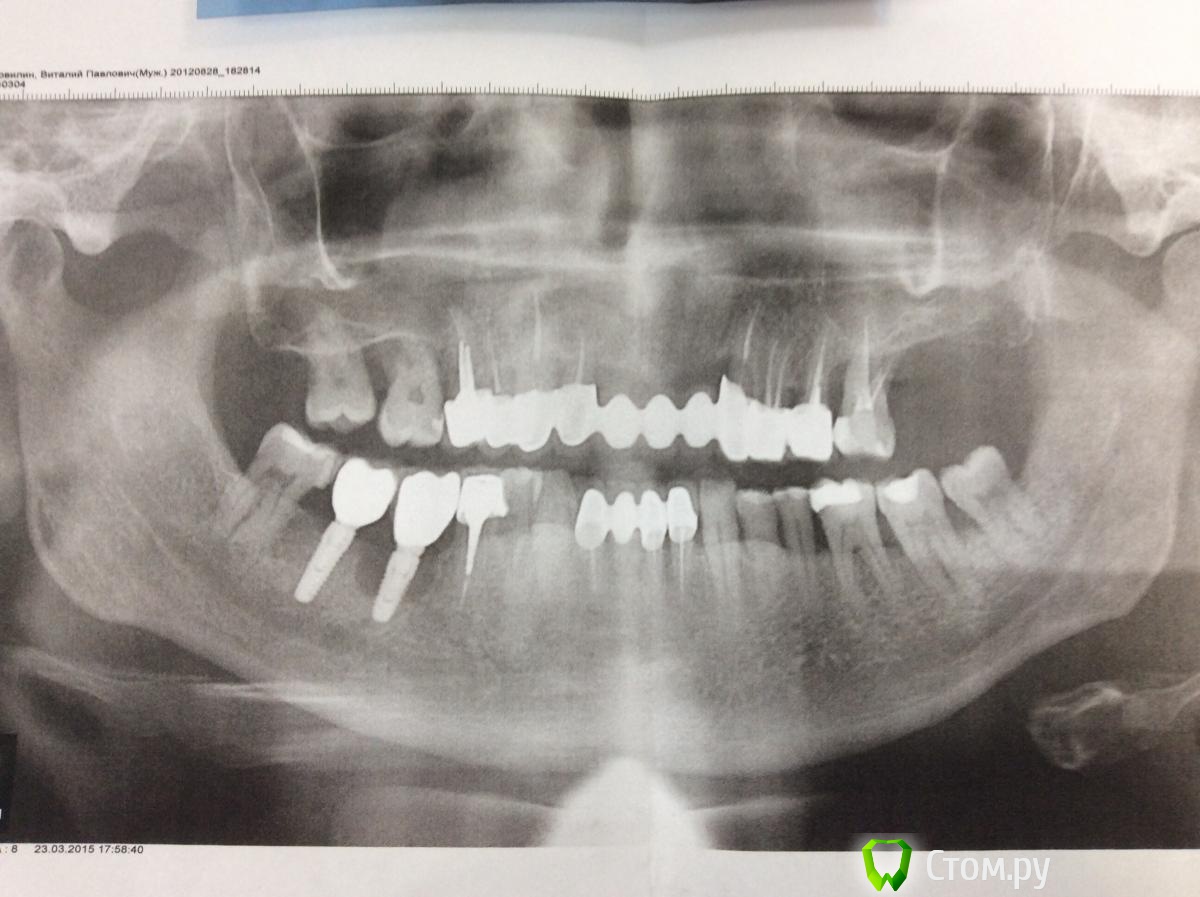

Opimar Опубликовано 10 апреля, 2014 Поделиться Опубликовано 10 апреля, 2014 Всем здравствуйте. Обратился пациент с жалобами на неприятный запах изо рта. На ОРТО вылезло вот это. В полости рта гноетечение из кармана. Подвижности имплантанта нет. Мысли удалить имплантант, откюретажить , оставить на 6 недель и сделать GBR с мембраной или ламиной. Прошу совета. Спасибо. Ссылка на комментарий

wladdX Опубликовано 11 апреля, 2014 Поделиться Опубликовано 11 апреля, 2014 Правильно думаете.Работа давняя? В чём причина, как думаете? Кератинизированная десна есть?У 48 "навес", обратите внимание. Ссылка на комментарий

Opimar Опубликовано 11 апреля, 2014 Автор Поделиться Опубликовано 11 апреля, 2014 (изменено) Корея? Сколько прошло с момента установки и протезирования? Какова причина, по Вашему мнению? Она самая CSM 4.2 на 10. Ставил не я. Установили 22.11.12 осмотры 4.12.12 и 15.01.13 жалоб нет но там походу и снимков не делали. А вот 5.03.13 в карте запись про наличие разряжения уже на 2/3 длинны. Потом вектром обработали имплантант osteomatrix и мембрана Ace. Ну и естественно толку ноль. 20.05.13 установили коронки. Ну и вчера ко мне пришел. На орто то что наверху выложил. Из причин ну либо перегрев либо гиперкомпрессия наверно. Изменено 11 апреля, 2014 пользователем Opimar Ссылка на комментарий